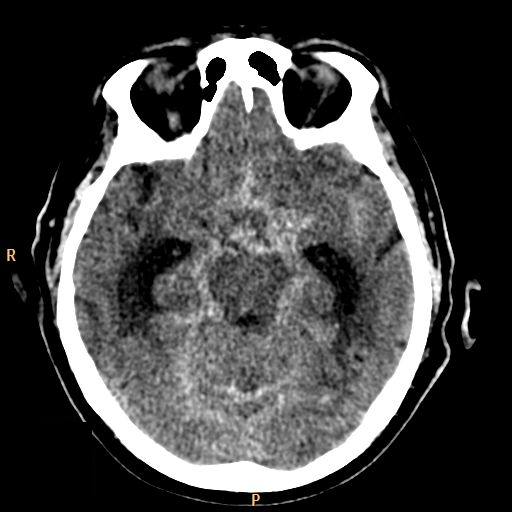

• Subarachnoid hemorrhage develops after vascular injury or aneurysm rupture.

6. Middle aged female fell of a ladder. On the unenhanced CT scan the basal cisterns are filled corresponding to a subarachnoid hemorrhage.